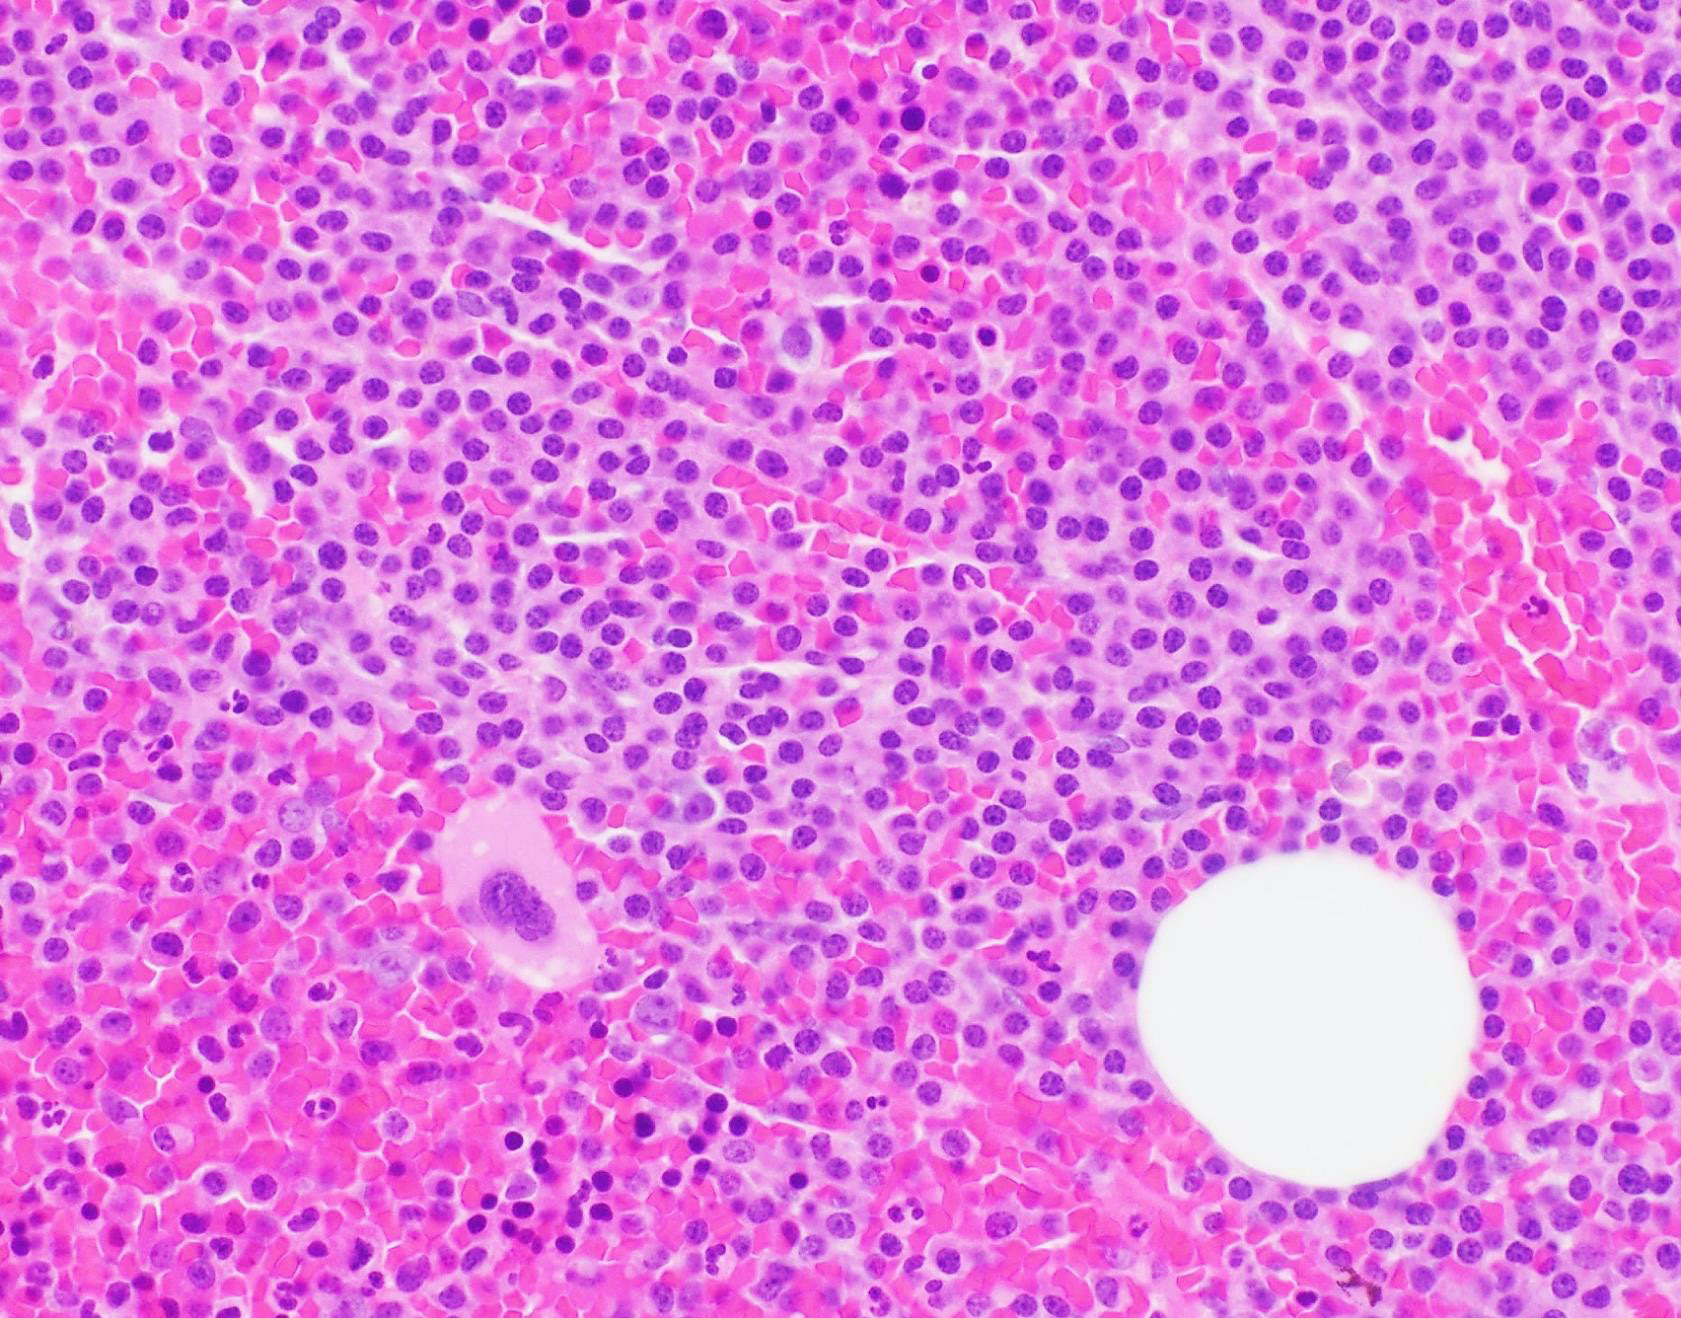

Microscopic (histologic) description

- Core biopsy (Am J Clin Path 1987;87:342):

- Interstitial clusters, nodules or sheets of plasma cells

- Areas of bone marrow may be spared with preserved hematopoiesis, other cases may have diffuse involvement and markedly suppressed hematopoiesis

- Prominent osteoclastic activity may be seen

Cytology description

- Cytology can assess plasma cell morphology (e.g., mature, immature, plasmablastic) but number of plasma cells present may vary substantially from the core biopsy

- Mature plasma cells: oval with abundant basophilic cytoplasm, perinuclear hof, round eccentric nuclei, clock face chromatin and indiscernible nucleoli

- Immature plasma cells: higher nuclear to cytoplasmic ratio, more abundant cytoplasm and hof region compared to plasmablastic, more dispersed chromatin, often prominent nucleoli

- Plasmablastic: less abundant cytoplasm with little or no hof region, fine reticular chromatin, large nucleus (> 10 microns) or large nucleolus (> 2 microns) (Blood 1998;91:2501)

- Pleomorphic: multinucleated, polylobated

- Rare cases may have small, lymphoid appearing plasma cells or plasma cells with marked nuclear lobation